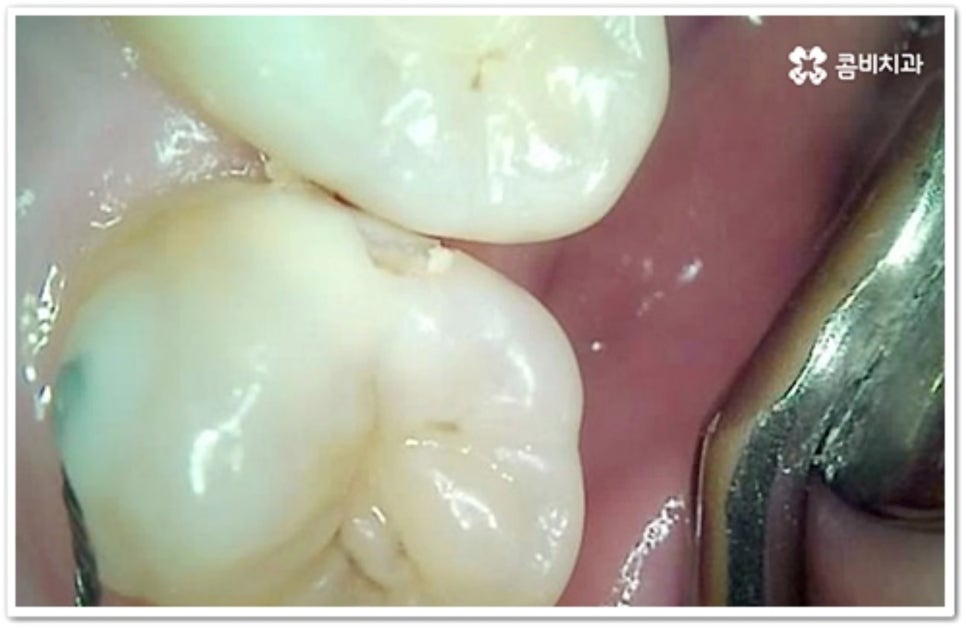

충치는 시간을 두고 단계적으로 진행하는 구강 질환이기 때문에 초기에 발견하여 빠르게 대처해 주는 것이 구강 건강을 위해 보다 바람직한 방법이라 할 수 있습니다. 흔히 우리가 충치라고 부르는 치아 우식증은 발생 위치에 따라 두 가지 종류로 나눌 수 있는데요. 보통 위아래 치아가 마주보는 교합면에 생기는 충치는 육안으로 발견할 가능성이 높고 접근이 용이하기 때문에 치료가 쉬운 편이지만, 치아 사이에 생기는 인접면 충치 는 맞닿은 치아로 인해 노출이 잘 되지 않기 때문에 발견도 어렵고 상황에 따라 치료할 때 기구를 손상 부위까지 닿게 하기 위해 치아 삭제가 많이 이루어져야 하는 경우도 있는 등 좀 더 까다로울 수 있어요.

하지만 앞니가 아닌 안쪽 어금니의 인접면 충치 라면 증상이 없고 발견이 쉽지 않기 때문에 초기에 발견하고 치료를 하는 것이 힘들 수 있어요. 그렇기 때문에 평상시에 꾸준히 검진을 받고 치실을 사용하여 칫솔질을 꼼꼼하게 해 주는 것이 더욱 중요한 거예요.